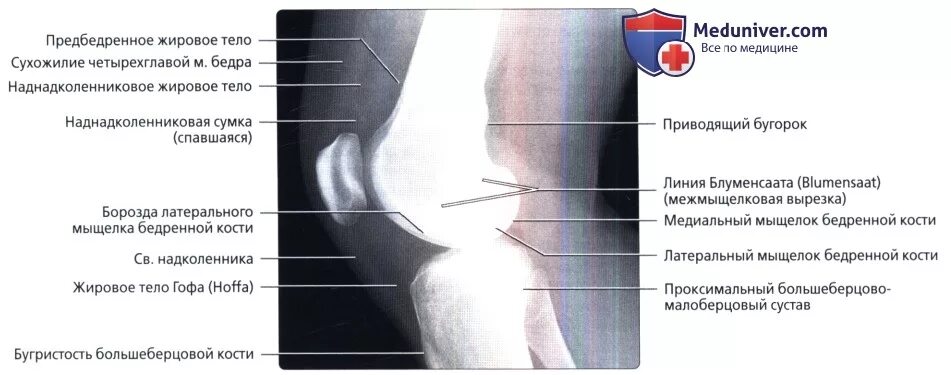

Обызвествление места прикрепления сухожилий